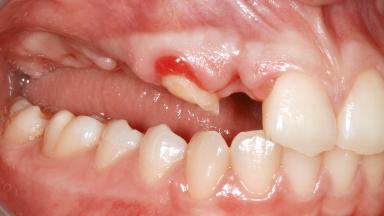

It is well known to clinicians that any removal of teeth will, over time, cause the dimensions of the alveolar ridge to be reduced by resorption of the bundle bone and by changes related to external modeling. This development is particularly evident in the crestal region with its thin buccal bone that consists of bundle bone almost entirely. The facial bone will rapidly resorb as blood supply from the periodontal ligament gets disrupted (Araújo and Lindhe 2005). There is no reason why traumatic tooth loss should not have the same consequences. It takes more than achieving implant osseointegration for a treatment outcome to be considered successful. No deficiency of bone or soft tissue is acceptable when an ideal esthetic outcome is the goal. Several articles (Sanz and coworkers 2011; Vignoletti and coworkers 2011) have reported on techniques of improving the alveolar ridge for implant treatment, notably focusing on protecting tissues from resorption.